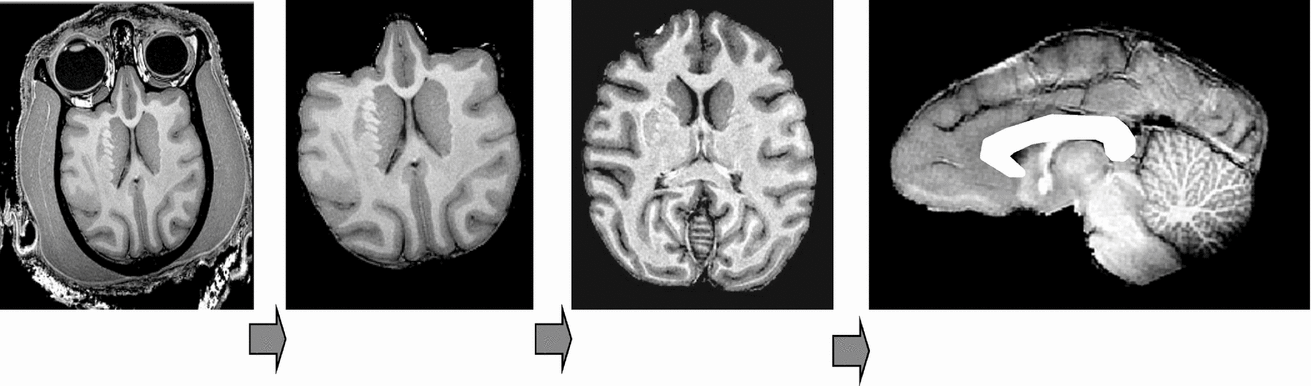

The image processing pipeline consisted of the following steps: removal of non-brain tissue, correction for spatial variations in intensity due to scanner radio-frequency inhomogeneity, and global spatial normalization to a population-based template to reduce global variability in brain size and orientation (Figure 1). The details of this processing are described elsewhere (Rogers et al., Reference Rogers, Kochunov, Lancaster, Shelledy, Glahn, Blangero and Fox2007). In short, the removal of non-brain tissue used both automatic (Smith, Reference Smith2002) and manual detailing methods. The correction for RF-inhomogeneity was performed using the functional magnetic resonance imaging of the brain (FMRIB) automated segmentation tool (Smith et al., Reference Smith, Jenkinson, Woolrich, Beckmann, Behrens, Johansen-Berg, Bannister, De Luca, Drobnjak, Flitney, Niazy, Saunders, Vickers, Zhang, De Stefano, Brady and Matthews2004). A nine-parameter global spatial normalization procedure was used to reduce inter-subject variability in global brain size, shape, and orientation, and was performed using the FMRIB linear image registration tool (Smith et al., Reference Smith, Jenkinson, Woolrich, Beckmann, Behrens, Johansen-Berg, Bannister, De Luca, Drobnjak, Flitney, Niazy, Saunders, Vickers, Zhang, De Stefano, Brady and Matthews2004). A population-based, pseudo-Talairach, median-geometry atlas served as the target brain for global spatial normalization. This atlas was created using methods previously described for humans (Kochunov et al., Reference Kochunov, Lancaster, Thompson, Toga, Brewer, Hardies and Fox2002) and primates (Kochunov & Duff Davis, 2009).

FIGURE 1 Structural image processing pipeline, which allows for a simple automation of sequential processing steps. Our pipeline consists of the following steps: removal of non-brain tissue, correction for RF-inhomogeneity artifacts, global spatial normalization (A), hemispheric segmentation (B), tissue classification (C), extraction of the inner/outer cortical surfaces (D, E), extraction of cortical sulci (F), automated labeling of cortical sulci (G), and gyral segmentation (H).